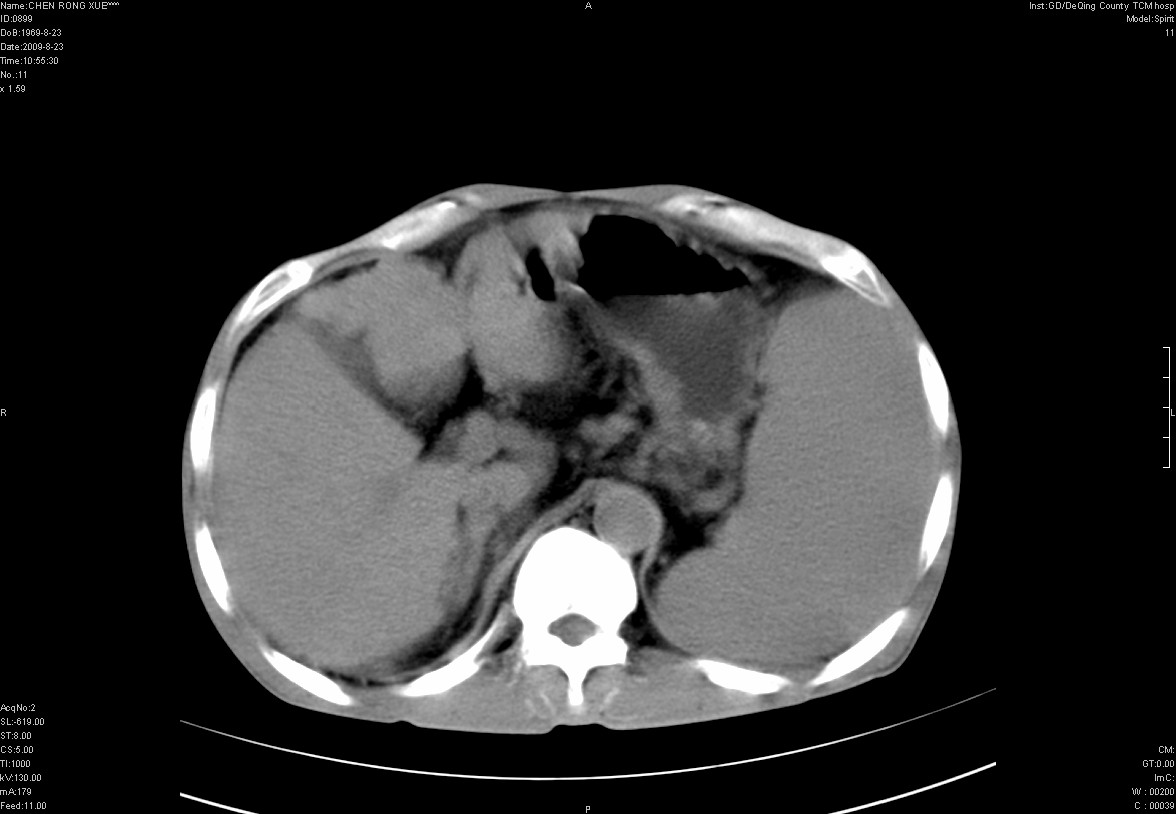

以下是引用zxl51642在2009-8-23 12:56:00的发言:[br]1、肝硬化、脾大;2、慢性胆囊炎;3、右肾占位并右侧腰大肌受侵,考虑恶性可能性大,建议增强扫描进一步检查。

以下是引用qiuleiyu在2009-8-23 15:17:00的发言:[br]1、慢性肝病,肝硬化,脾大,门脉高压。胆囊小结石。[br]2、右肾明显肿大,伴片状低密度灶,累及右侧腰大肌,肿瘤及炎症性病变皆有可能大,建议增强。

以下是引用zjzjr在2009-8-23 17:42:00的发言:[br]1、慢性肝病,肝硬化,脾大,门脉高压。胆囊小结石。[br]右肾脓肿波及肾周,建议增强